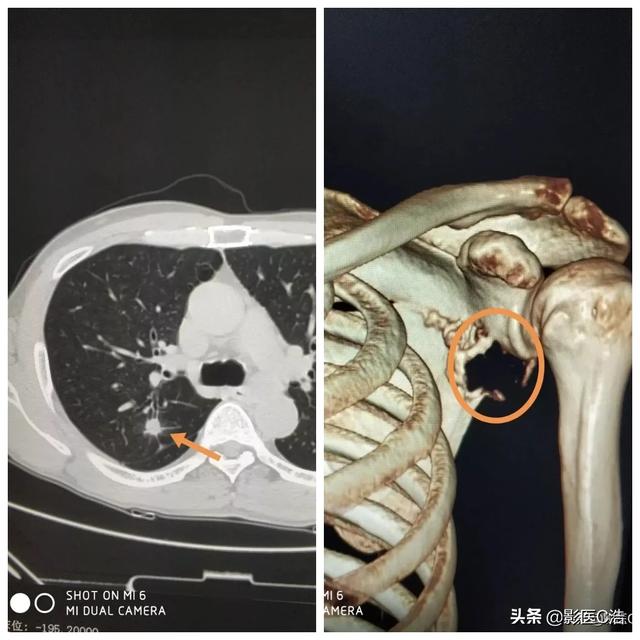

Métastase claviculaire d'un carcinome peu différencié ayant survécu à la tumeur pendant 5 ans.

Il s'agit d'un homosexuel de 58 ans qui a commencé à ressentir une douleur persistante lorsque son épaule a été légèrement étirée, et les radiographies ont révélé des foyers hypodenses :

Il s'agissait d'une fracture pathologique causée par des forces externes mineures sur la base d'une métastase osseuse. Une ponction a été effectuée et la pathologie était une métastase osseuse d'un adénocarcinome pulmonaire peu différencié.

Ce nodule irrégulier dans le poumon gauche est le foyer principal, qui ne mesure que 2,6 cm. Un cancer du poumon avec des métastases osseuses comme celui-ci n'est plus opérable. On ne peut rien y faire, le cancer du poumon est trop fréquent et certains des premiers symptômes sont atypiques, voire asymptomatiques.Dans environ 30 % des cancers du poumon, les symptômes des métastases sont la première manifestation, et les métastases sont détectées en premier avant que d'autres cancers du poumon ne soient détectés.

Heureusement, ce patient a été sensible au traitement et a été traité pendant 5 ans avec une combinaison de chimiothérapie et de traitements basés sur la thérapie ciblée.

Il s'agit de l'opération de fixation interne qu'il avait réalisée à l'époque pour une fracture de la clavicule, une fracture pathologique qui a beaucoup de mal à guérir seule sans intervention chirurgicale.

Son examen tomodensitométrique le plus récent a montré que la photo primaire avait beaucoup rétréci et il a eu la chance de survivre avec une rétention pendant plus de 5 ans !